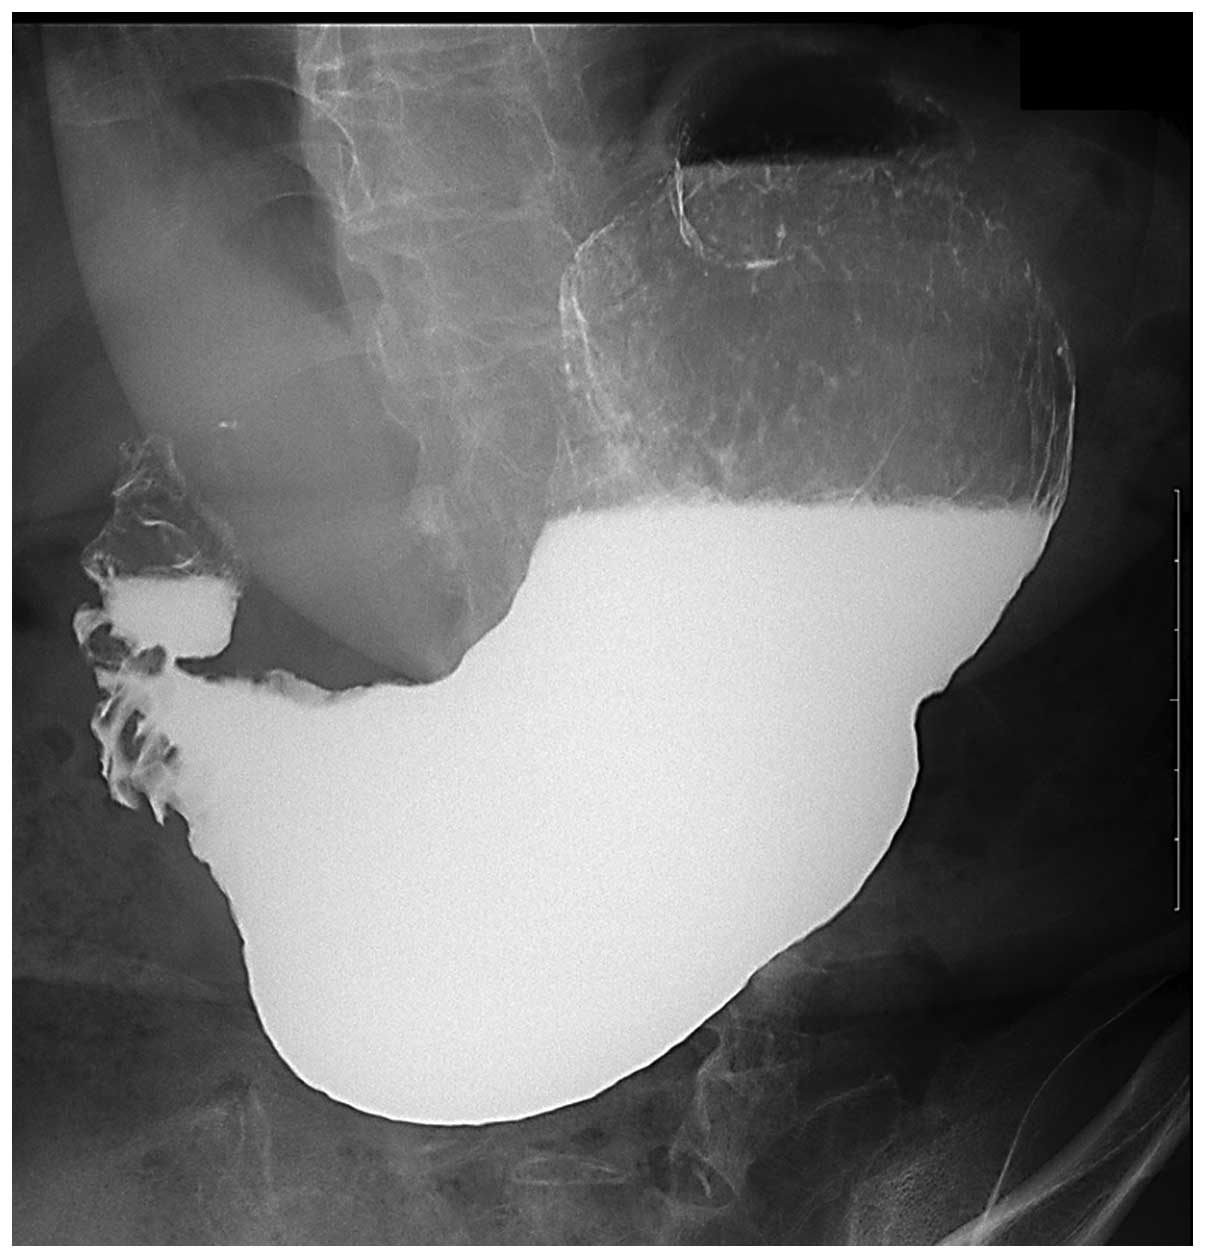

Снимки рентгена живота: примеры и случаи